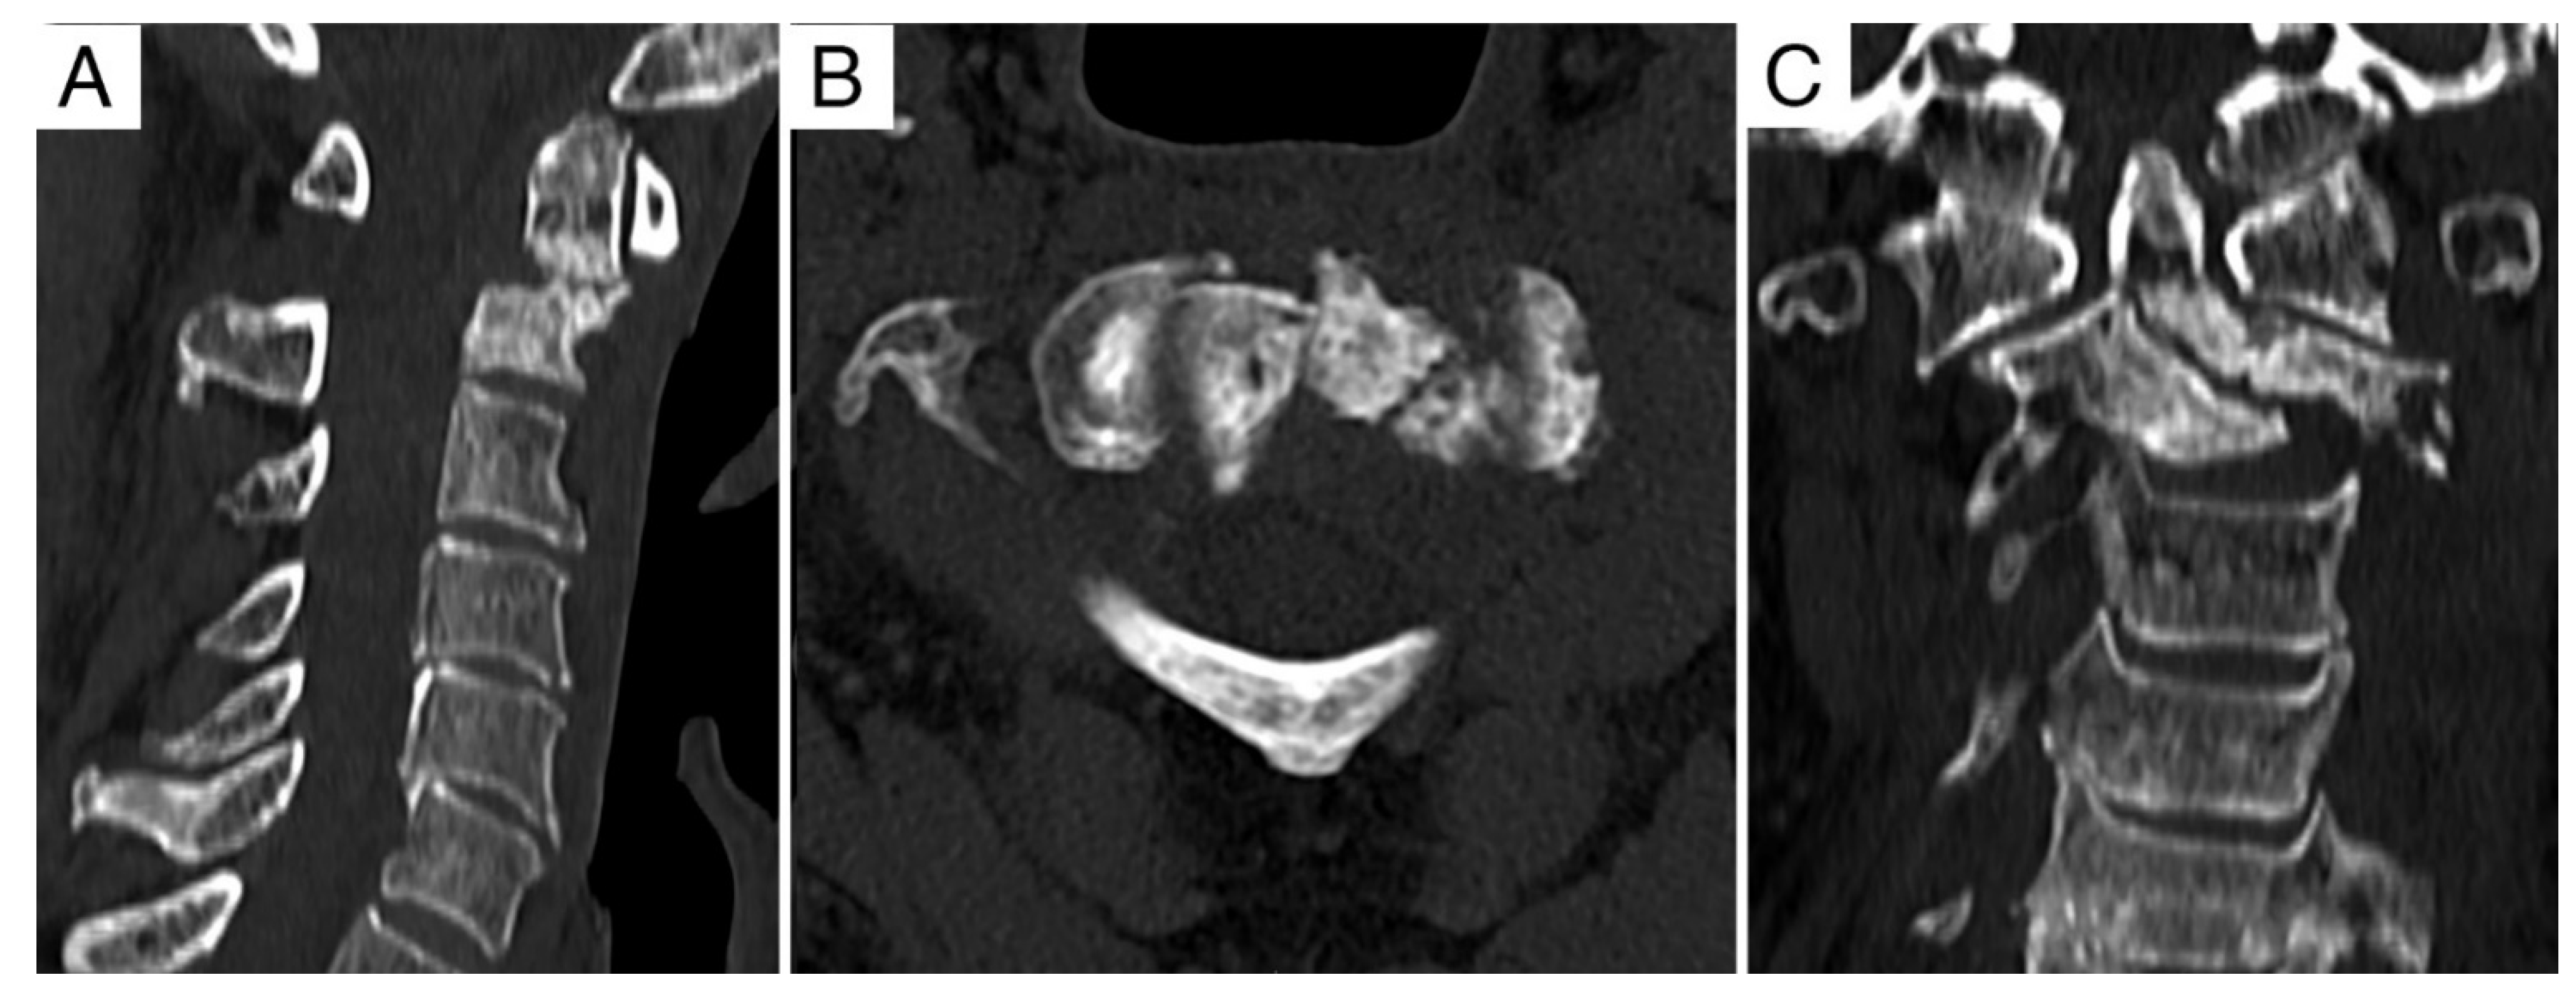

3.2. Case Report 2

| 2 | 75, M | Recurrent chordoma C2 | IB | 8-3/A-D | Extracapsular debulking (Δt = 8 m) RT (74 Gy proton-ion, Δt = 2 m) | A+P | Intralesional | 12 | 32 | DOD |